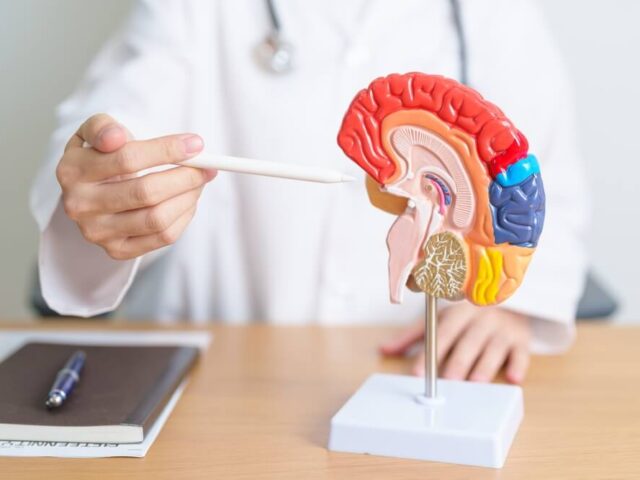

Pročitajte višeKako hiperbarična komora pomaže oporavak nakon moždanog udara?

Moždani udar predstavlja jedno od najozbiljnijih neuroloških stanja i jedan je od vodećih uzroka invaliditeta širom sveta. Nastaje kada se...